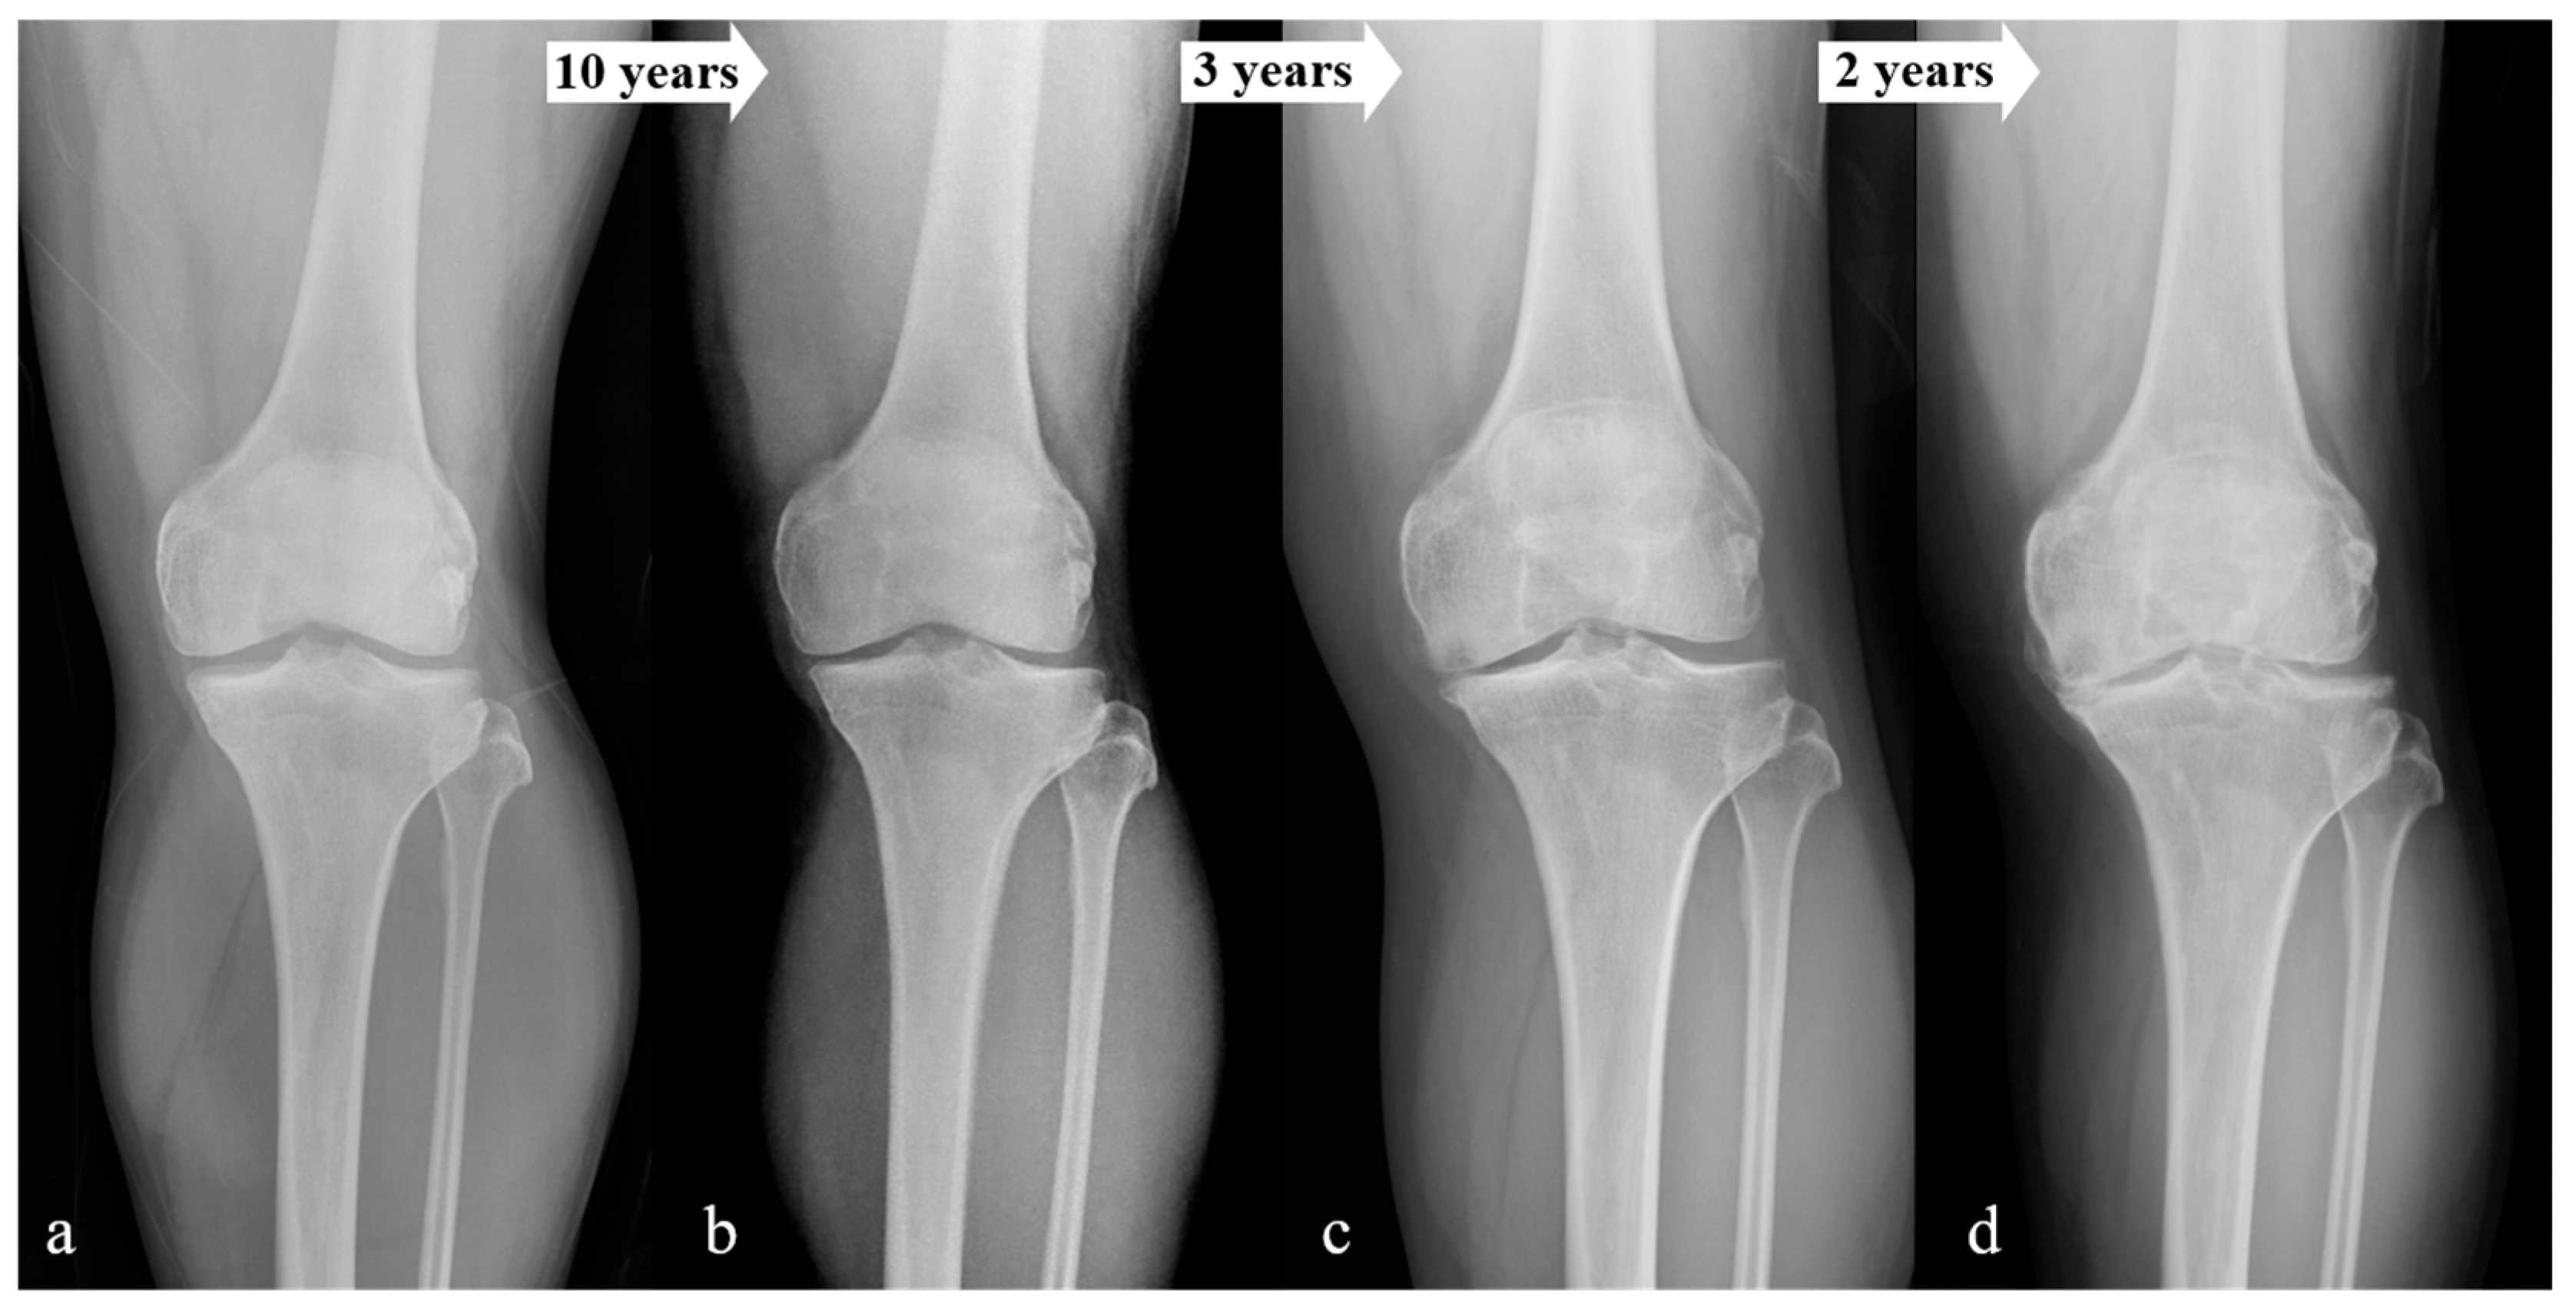

2.1. Classification

3. Results